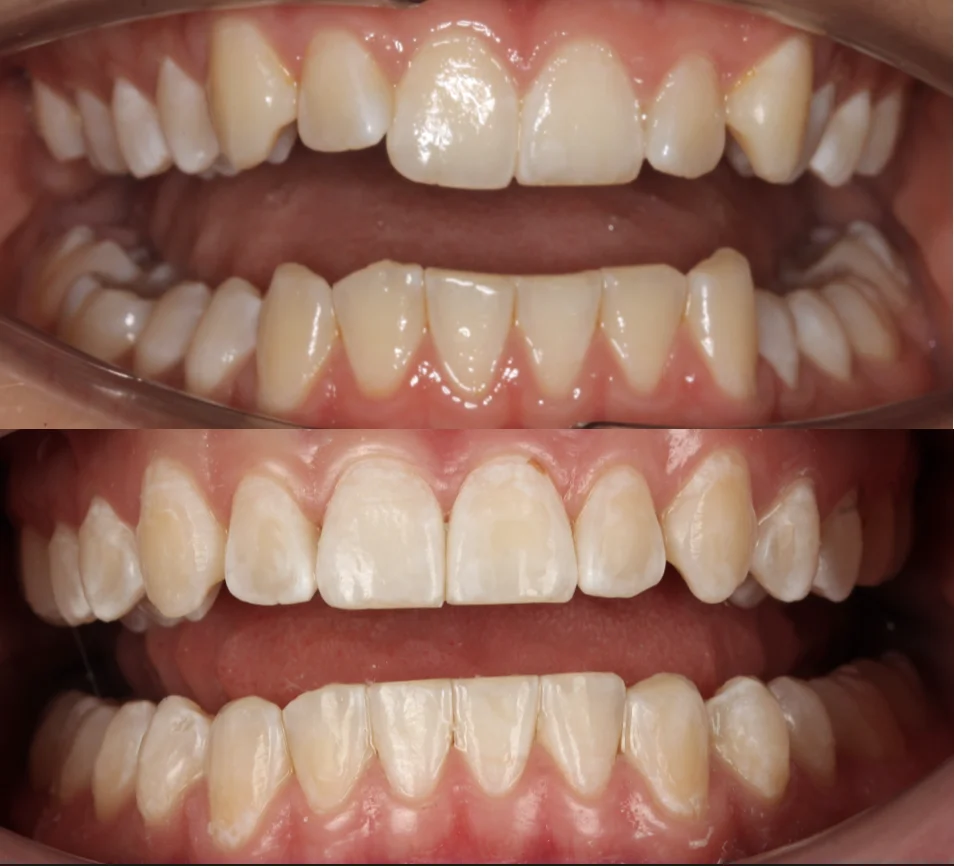

Проблема: В клинику обратился мужчина с жалобами на неправильное положение зубов и смыкание — ряды сходились некорректно, зубы стояли со смещением. При этом было важно, чтобы лечение оставалось незаметным для окружающих, поэтому вариант с брекетами не рассматривался.

Решение: Поставили элайнеры Invisalign на обе челюсти. Лечение заняло 4 года — случай потребовал нескольких этапов коррекции, каждый из которых последовательно приближал зубы к нужному положению. Капы менялись каждые 1–2 недели, контрольные визиты — для отслеживания прогресса и выдачи новых наборов. Зубы встали на место, смыкание пришло в норму. Зафиксировали ретейнеры на обе челюсти, пациент направлен к ортопеду для завершающего этапа.

Зубы выровнены, смыкание нормализовано. Установлены несъёмные ретейнеры на обе челюсти. Пациент направлен к ортопеду.